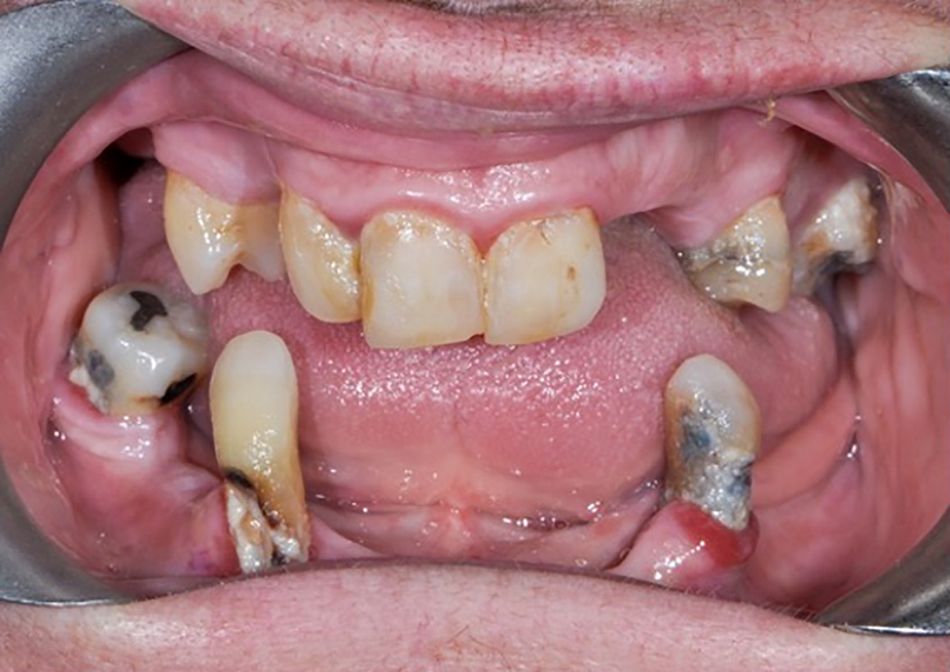

On presentation she had many missing teeth and carried upper and lower partial dentures, which she had for 30 years but has not been able to wear at all since the loss of tooth 34 shortly prior to her presentation, which served as the last remaining natural occlusal stop. She had severe oral dysfunction and was unable to bite or chew numerous foods. She was embarrassed to smile. (Fig. 1)

Oral hygiene was poor, and the remaining natural teeth had mild periodontitis with generalized horizontal bone loss (20% in the upper and 40% in the lower). The teeth were structurally compromised from large restorations and recurrent caries, and some were affected by drifting and/or supraeruption. The skeletal bases were in a Class 2 Div 2 correlation, and there was a gross collapse of the Occlusal Vertical Dimension with no stop by any natural teeth. (Fig. 2, 3, 4)